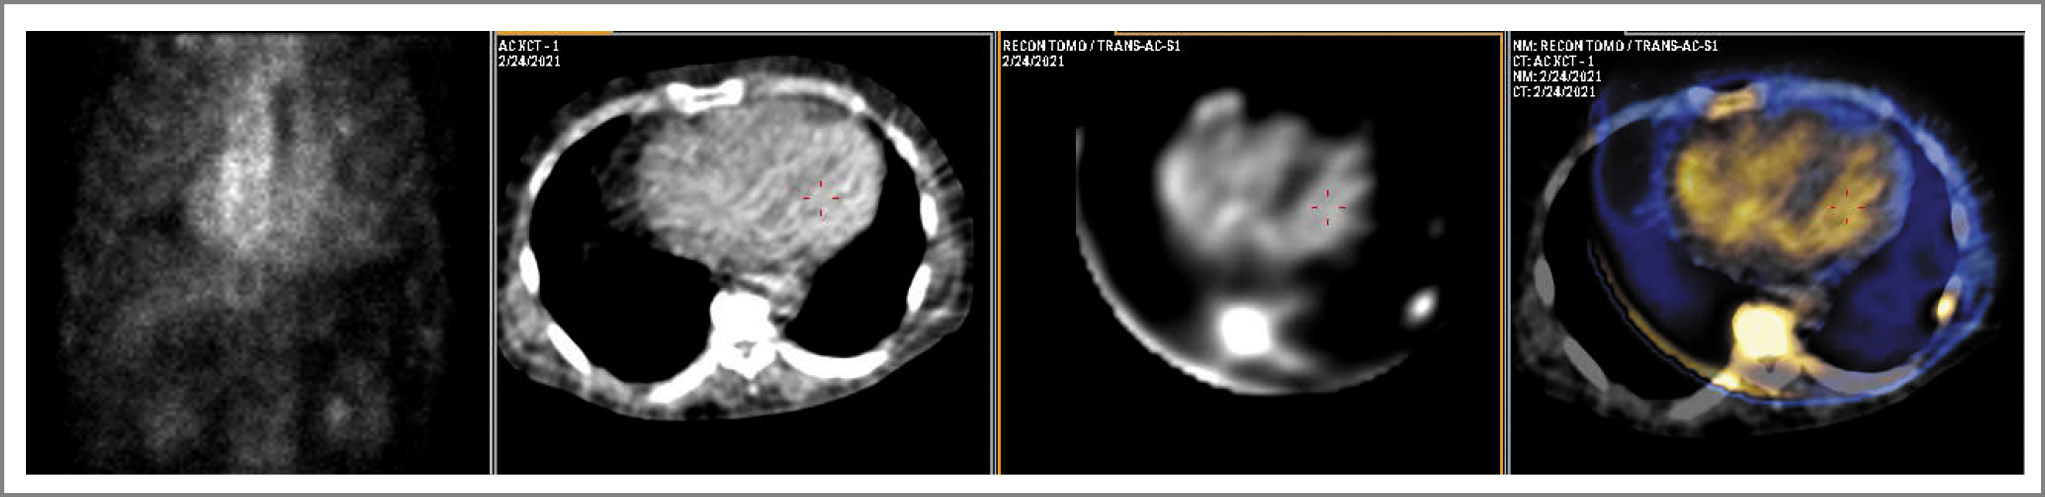

Интерпретация исследования у 2 пациентов с Grade 3 не вызвала затруднений ввиду интенсивного накопления РФП в миокарде, значительно перекрывающего сигнал не только от полостей сердца, но и от костных структур (рис. 4). У одного из этих пациентов (возраст 74 года, H/Cl=1,94) диаг- ностирован дикий тип (ATTRwt), у другого (возраст 47 лет, H/Cl=2,50) выявлена мутация в гене TTR.

Рис. 4. Данные планарной сцинтиграфии, КТ, ОЭКТ и ОЭКТ/КТ пациента с верифицированным TTR-амилоидозом. Отмечается тотальное высокоинтенсивное накопление 99mTc-PYP в миокарде (Grade 3). / Fig. 4. Data from planar scintigraphy, CT, SPECT and SPECT/CT of a patient with verified TTR-amyloidosis. There is a total high-intensity accumulation of 99mTc-PYP in the myocardium ( Grade 3).